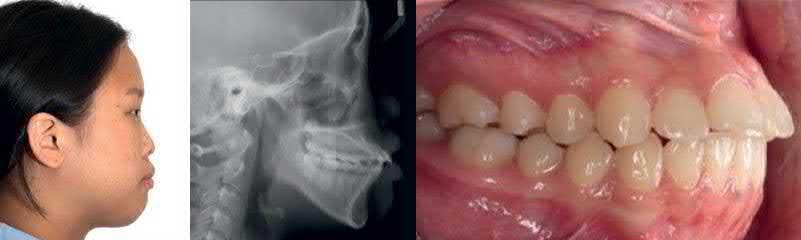

Figure 1.3  Class I correction with a palatal plate and TADs [11, 13]. (a) Initial examination indicated Class I malocclusion with the proclined maxillary incisors and protrusive lips. (b) A palatal anchorage plate was placed. (c) Retractive force direction can be controlled by engaging elastomeric chains at different levels of the hooks. (d) The mandibular arch was retracted using Class III elastics. (e) Maxillary and mandibular anterior teeth were retracted. Facial harmony and lip support were significantly improved.

Source: Kook et al. [11]. Reprinted with permission from Elsevier.